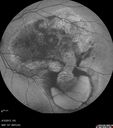

INDOCYANINE GREEN ANGIOGRAPHY: The indocyanine green angiogram in the left eye shows early polypoidal choroidal vasculopathy with a clear lacy network with polyps temporal to the fovea. In the right eye in the late frames, the entire lesion stains. The right eye similarly has a staining lesion centrally suggesting an occult subfoveal choroidal neovascular membrane.

Idiopathic Polypoidal Choroidal Vasculopathy - Indocyanine Green Angiogram - Polyp Visible Left Eye. Branching Network Both Eye740 views     (0 votes)

Idiopathic Polypoidal Choroidal Vasculopathy - Indocyanine Green Angiogram - Polyp Visible Left Eye. Branching Network Both Eye692 views     (0 votes)

Idiopathic Polypoidal Choroidal Vasculopathy - Indocyanine Green Angiogram - Polyp Visible Left Eye. Branching Network Both Eye675 views     (0 votes)